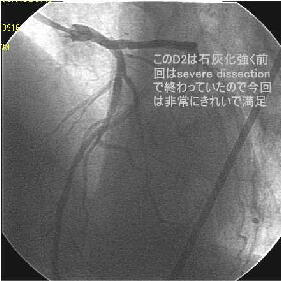

�܂�pre CAG.

|

|

|